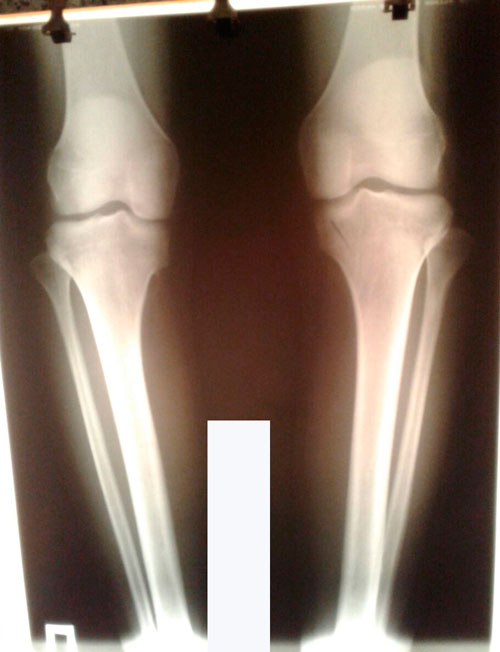

Исходник - 19 лет.

Дата операции 25.05.2017г.

Дата снятия аппаратов 10.08.2017г.

Срок лечения 75 дней.

PS. Этот ребёнок приехал к нам с "кучей" комплексов: зажатая, испуганная и не уверенная в себе девочка. Она стеснялась своих ног.

Теперь она с гордостью будет носить новые ножки и радовать их красивыми нарядами!